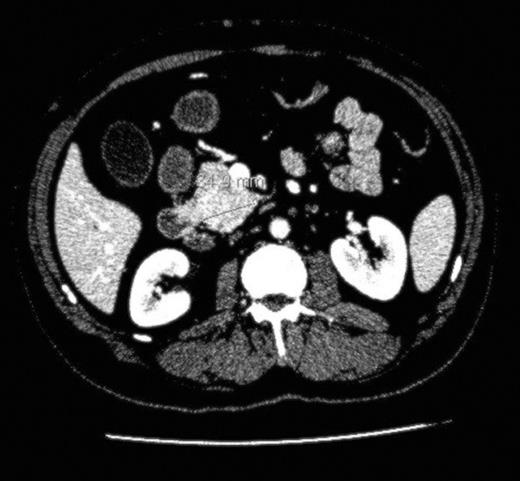

We report the case of a 61 year old man, previously treated for follicular lymphoma in the left groin with radiotherapy, presentING to our hepatobiliary department with painless obstructive jaundice ALP 592 iu/L (40-130), ALT 86 iu/L (2-53) and Bil 180 (3-17). His CA19.9 was 156 u/l and there was no clinical evidence of tuberous sclerosis. Cross-sectional imaging in the form of a CT and MRI scan reported multiple suspicious lesions in the liver (Fig. 1) and a small lesion in the uncinate process of the pancreas (Fig. 2) causing intrahepatic and common bile duct dilatation. The radiological diagnosis at this point was of a metastatic (and hence inoperable) pancreatic cancer. He underwent an ERCP and insertion of a CBD stent to relieve his jaundice and an attempted percutaneous biopsy of his pancreatic mass yielded inadequate cells. He then underwent a laparoscopy and attempted biopsy of his pancreatic and/or liver lesions. The pancreatic mass was difficult to visualise on intraoperative ultrasound however one of the liver lesions was biopsied and this was reported as an angiomyolipoma.